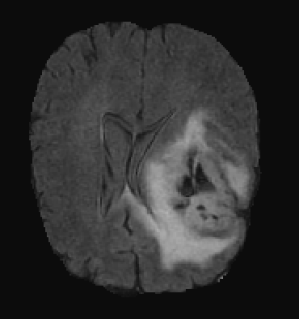

3.3 Visual analysis

Figure 5 shows two subjects among the quantitatively better (first row) and poorer (second row) results. In both cases, it can be visually appreciated that our method correctly segments the whole tumor region. For the subject shown in Figure 5.a, the system is able to properly capture all tumor regions, meaning that the first network is able to correctly localize the tumor and the second network is able to capture differences between tumor regions. On the other hand, in Figure 5.b, we show a case where even though the tumor is correctly localized by the first network, the second isn’t able to properly detect different tumor subregions. We see that edema (ED - label 2) is overrepresented in our segmentation in detriment of smaller classes: GD-enhancing tumor (ET - label 4) and the necrotic and non-enhancing tumor (NCR/NET - label 1). This effect can also be inferred from lower values in ET and TC dice coefficients.